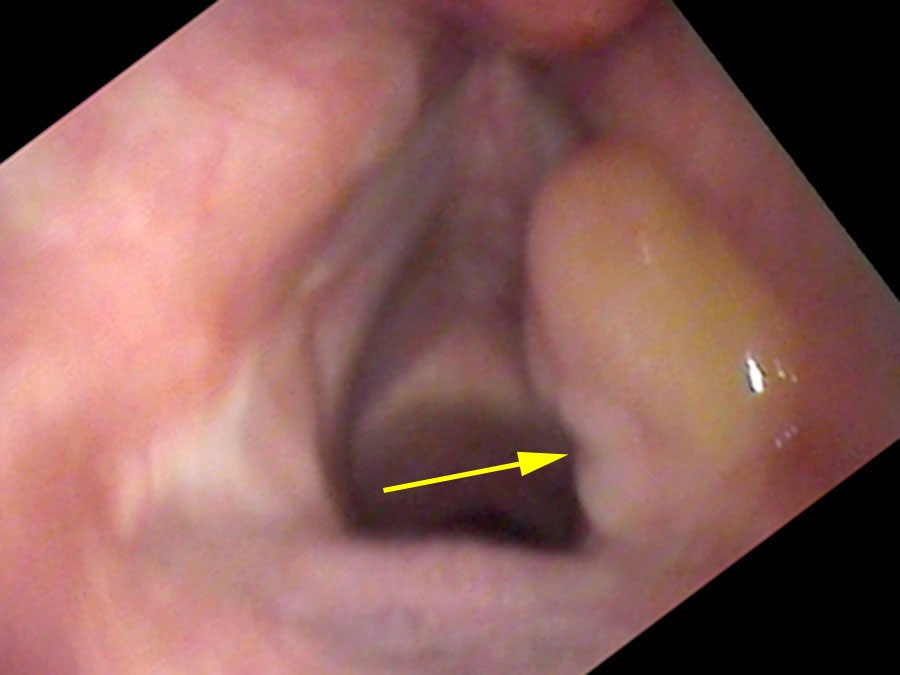

From injury to resolution, granulomas follow a predictable evolution. New ulcers from overuse initially split into two parts where the opposite vocal process rests in a groove during closure. Gradually, granulation tissue heaps up around the traumatized point, forming a mass. In the middle of their lifespan granulomas become yellow or red and round. Later the mass tends to harden, become white and spherical, and the base narrows to a stalk. At this stage the granuloma may flip up out of the way during phonation and no longer impairs closure — so vocal capabilities testing can return to normal even while the granuloma is still present.

Eventually the granuloma hangs from a thinner and thinner stalk before it falls off or is coughed off. Sam came back a year later: “About two weeks ago I was yelling at a baseball game. I coughed out something that looked like a BB and felt a sharp pain on the left side of my throat.” The self-decapitation of the granuloma is a common and self-limiting event — though as long as the underlying cause persists, recurrence is expected.